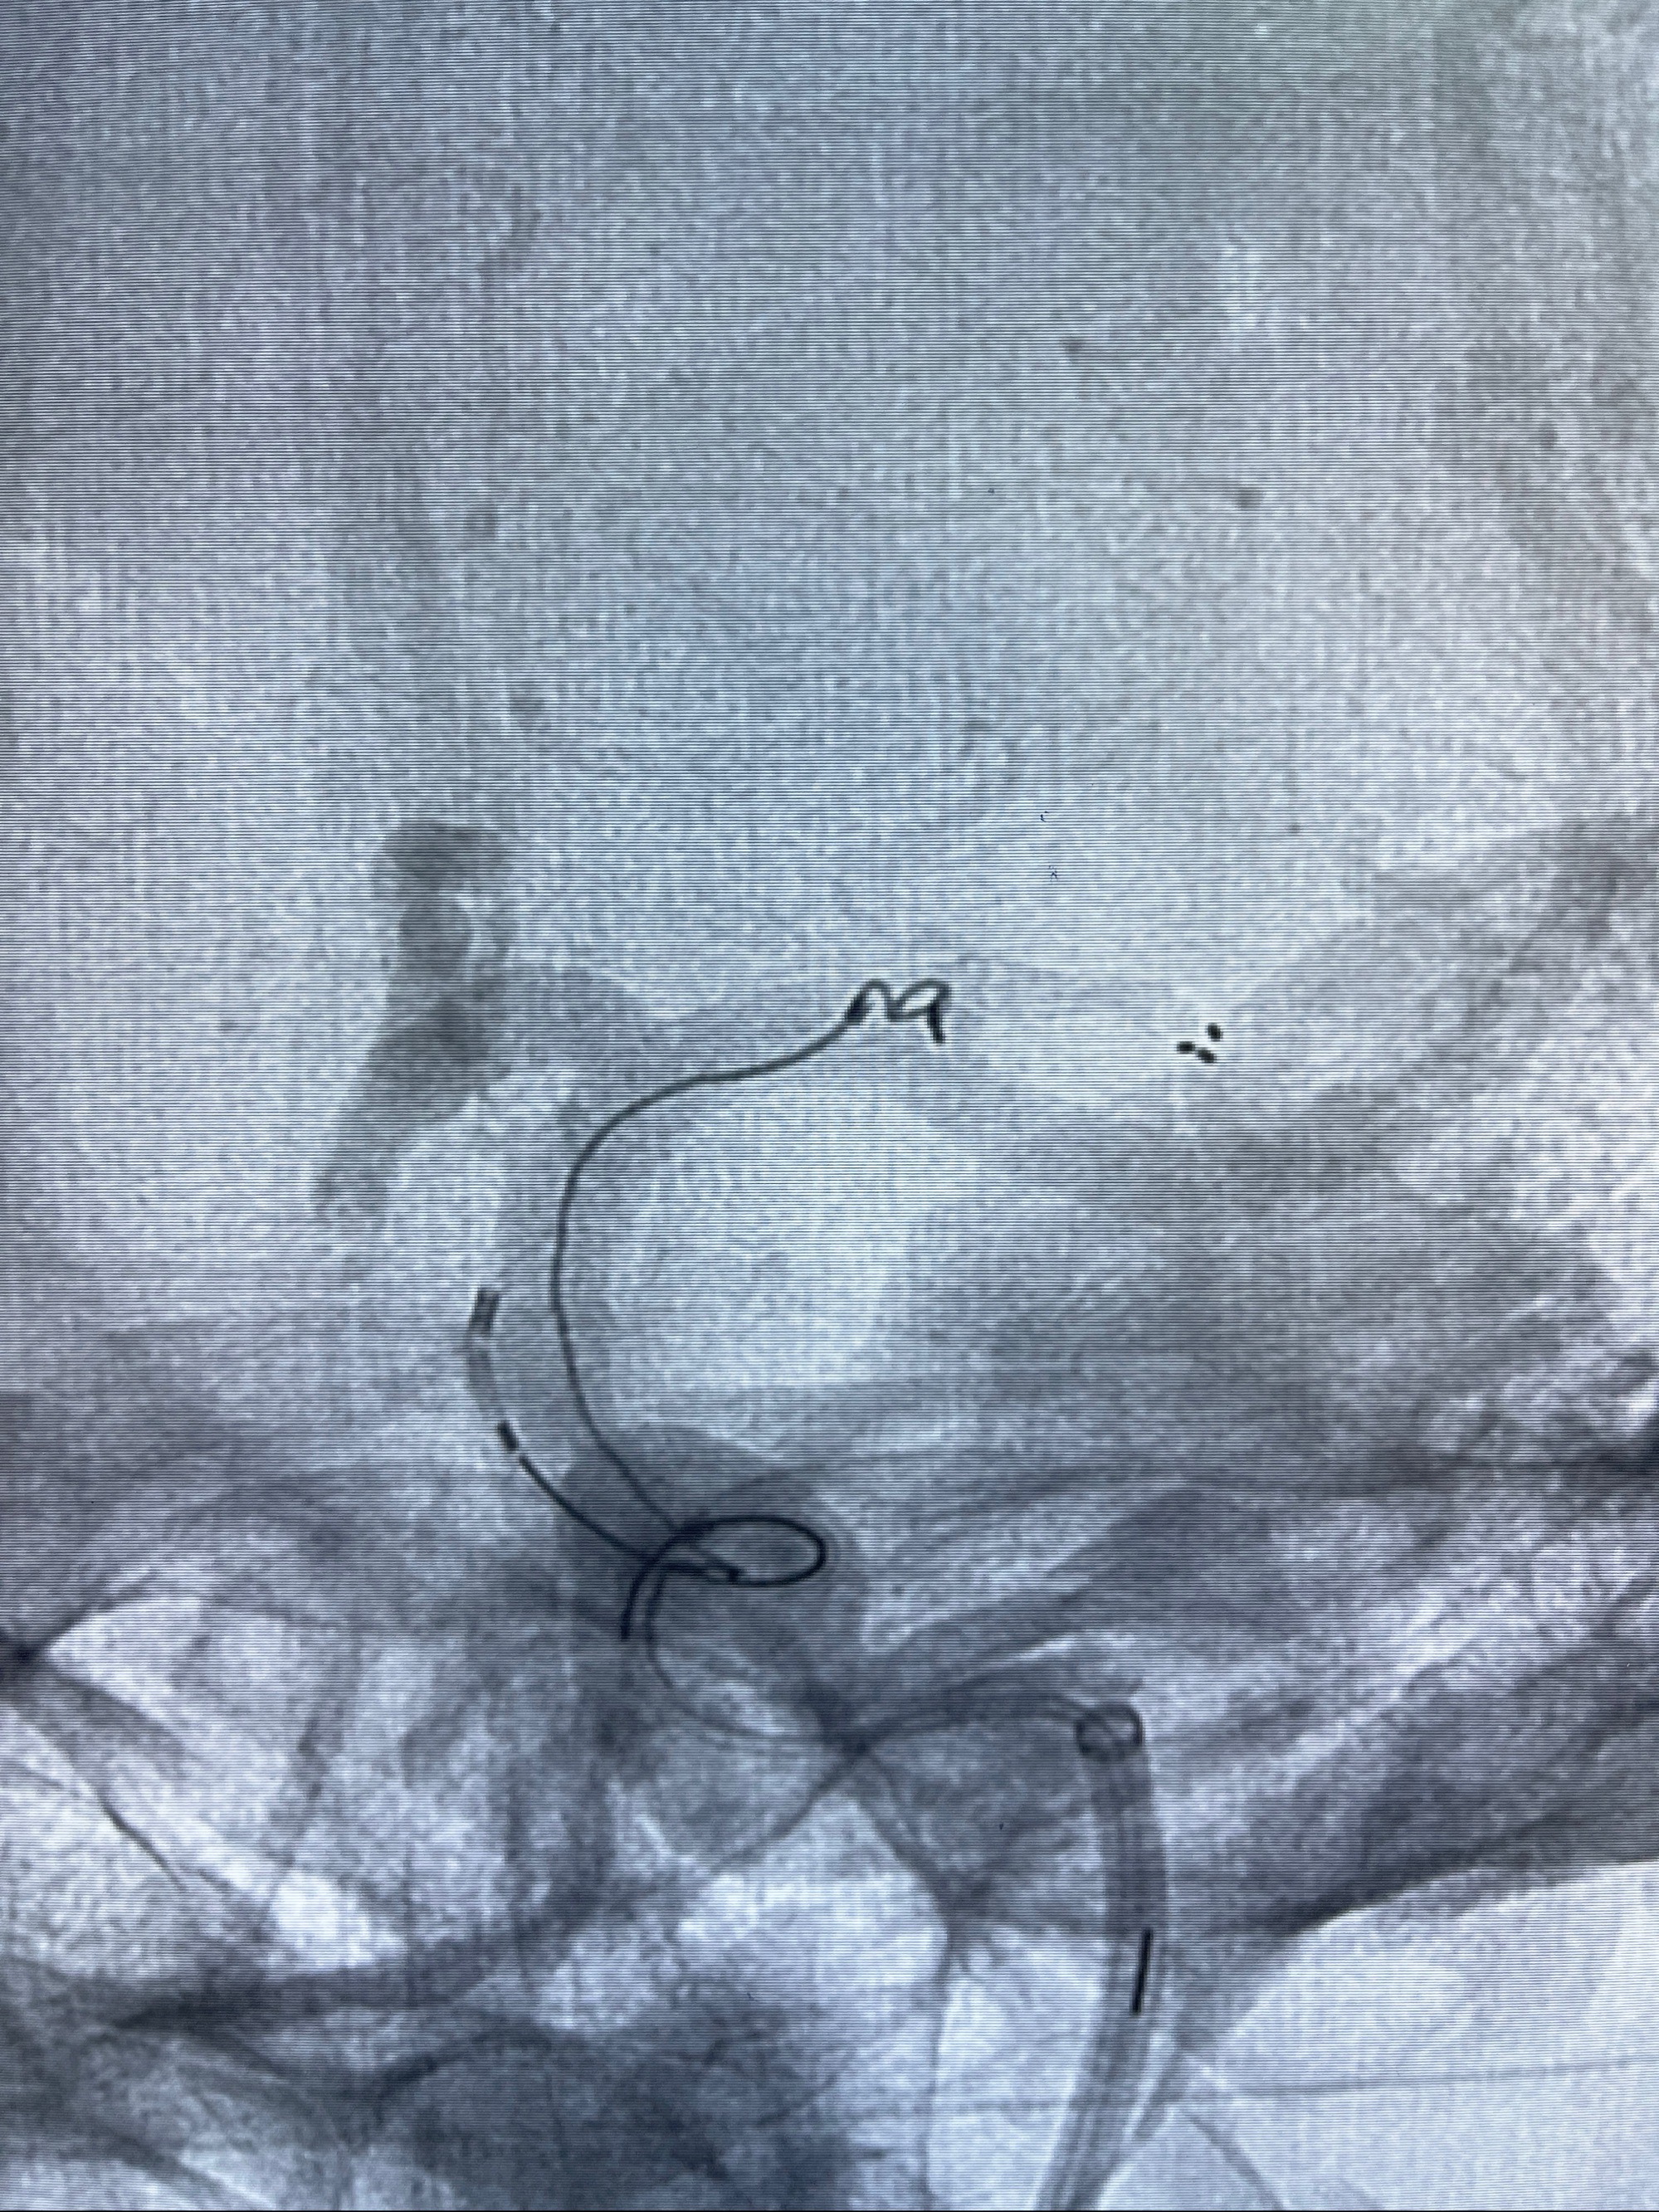

麻醉苏醒佳,遵嘱动作

术后即刻CT